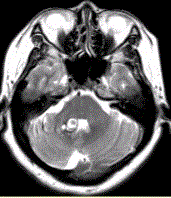

问题 患者女,41岁。头痛半年,加重10d。头部MRI显示如下图。 关于该病的MRI描述正确的是

选项 A.右侧小脑半球圆形长T2信号影,病变周边可见环形低信号 B.病变周边环形低信号对病变的诊断价值不大 C.病变邻近右侧小脑半球可见一条形高信号,其对病变的诊断价值不大 D.病变邻近右侧小脑半球可见一条形高信号,其对病变的诊断价值较大 E.第四脑室受压变窄对于病变的诊断价值较大 F.病变的内部信号不均匀对病变的诊断价值较大

答案 ADF